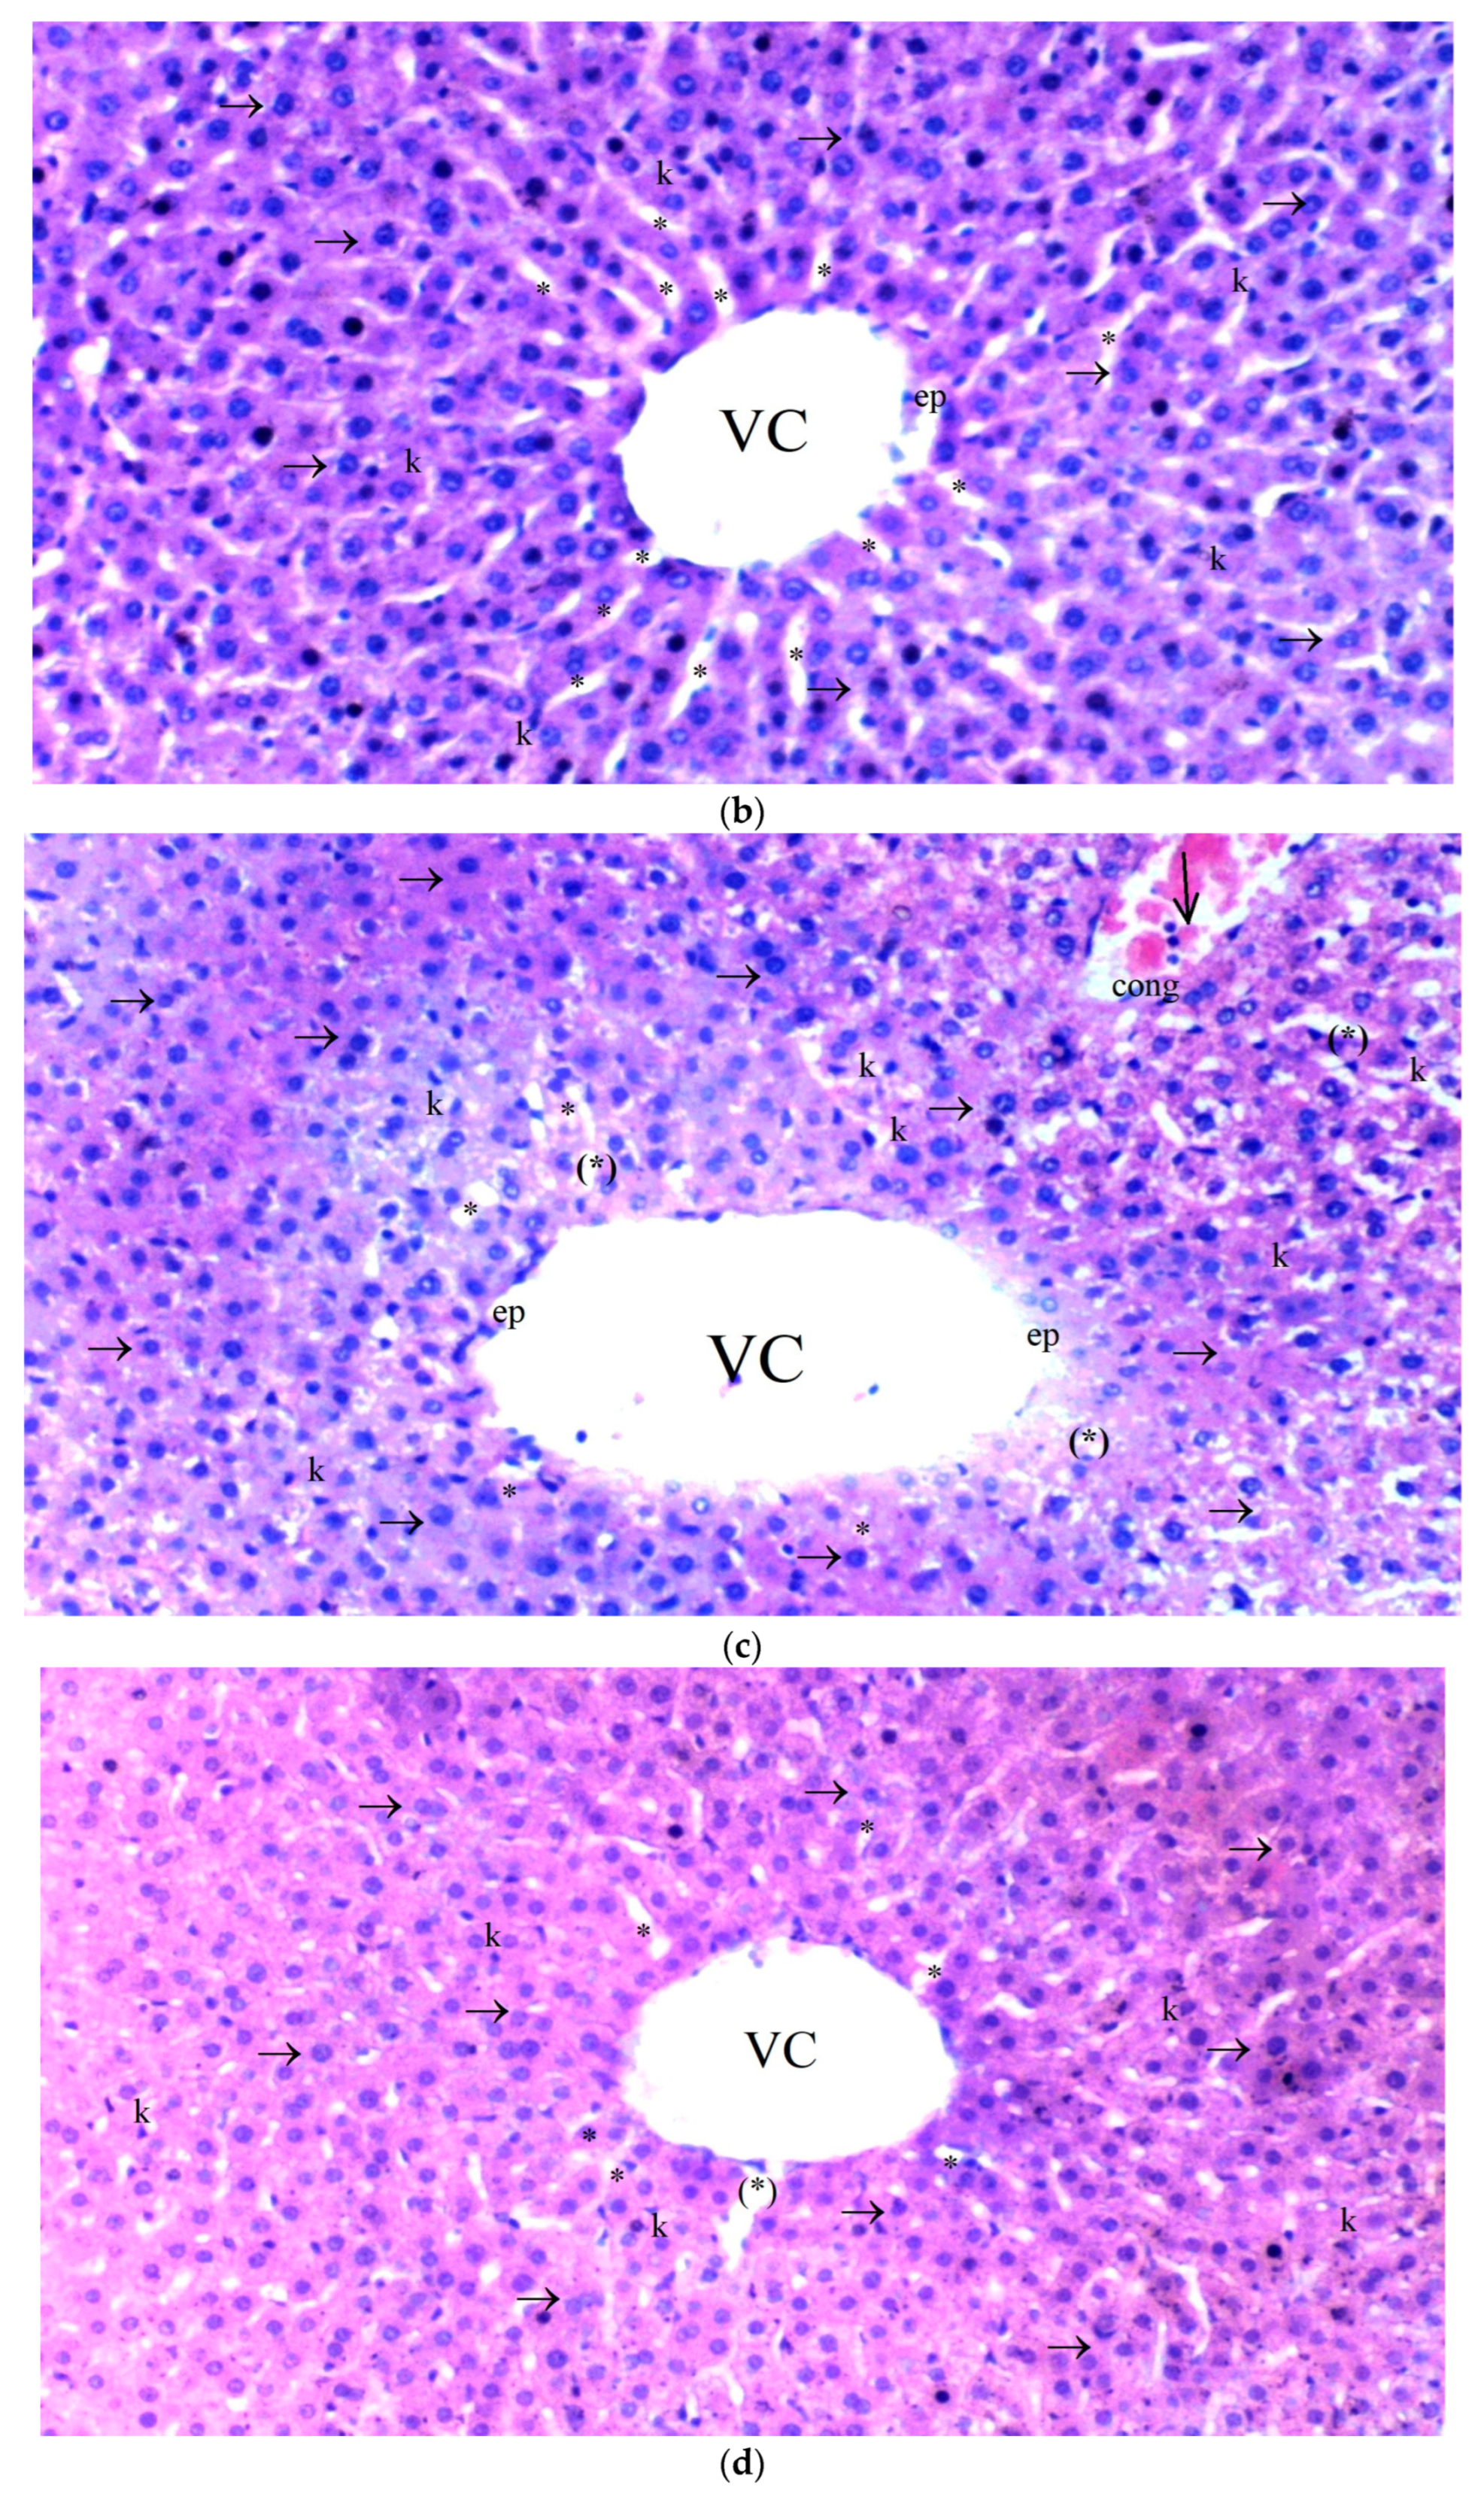

3.2.3. Liver Tissue

Significant differences were observed among the groups in terms of hepatocyte degeneration (p = 0.030). Hepatocyte degeneration was more prominent in the IR group compared to the control and BPC groups (p = 0.010 for both) (Table 6, Figure 3).

Figure 3.

(a–d) Histopathological examination of liver tissues of C, B, IR and IR-BPC groups. (a): Normal liver tissue in group C, (b): liver tissue of group B, (c): liver tissue of group IR with increased necrotic cells and hepatocyte degeneration, (d): liver tissue of group IR-BPC with mild degeneration compared to group IR. Abbreviations: ep—epithelium, vc—vena centralis, hl—hepatic lobule, →—hepatocytes, k—Kupffer cells, *—sinusoids, (*)—sinusoid dilatation, cong—capillary congestion, ↓—parenchyma.

Sinusoidal dilatation also differed significantly between the groups (p = 0.040). The IR group showed a higher degree of sinusoidal dilatation compared to the control and BPC groups (p = 0.013 for both). In contrast, sinusoidal dilatation in the IR-BPC group was significantly reduced compared to the IR group (p = 0.042) (Table 6, Figure 3).

Pyknosis (shrunken nuclei) was found to be significantly different among the groups (p = 0.025). Pyknosis was more frequently observed in the IR group compared to the control and BPC groups (p = 0.008 for both) (Table 6, Figure 3).

The number of necrotic cells was significantly different between the groups (p = 0.010). The IR group exhibited more necrotic cells compared to the control and BPC groups (p = 0.004 for both). However, the IR-BPC group showed a significantly lower number of necrotic cells compared to the IR group (p = 0.012) (Table 6, Figure 3).

Mononuclear (MN) cell infiltration in the parenchyma also showed significant differences among the groups (p = 0.027). The IR group had significantly higher levels of MN cell infiltration compared to the control and BPC groups (p = 0.009 for both). In the IR-BPC group, MN cell infiltration was significantly lower than in the IR group (p = 0.032) (Table 6, Figure 3).